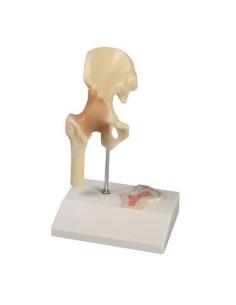

Modèle de maladie de l'articulation de la hanche 3B Scientific 1019506